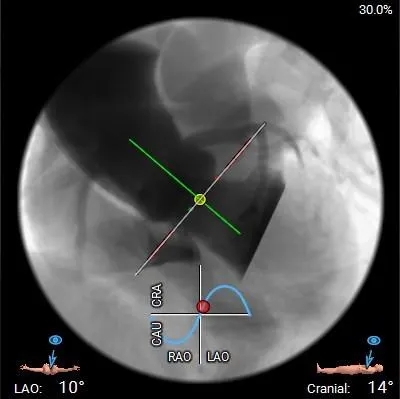

工作体位

右窦中心

左右重合

左冠切线